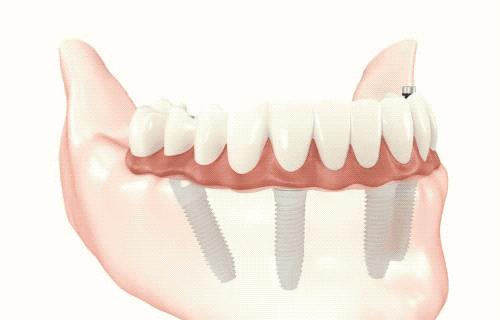

种植牙就是在我们缺失牙齿的区域,将种植体(人工牙根)植入骨头内,几个月后,种植体与牙槽骨完成紧密骨结合,能在骨头内能够稳固生存,再在种植体的上面接上烤瓷牙恢复牙齿的形态和功能。所以,种植牙就是用种植体代替天然牙根、烤瓷牙恢复牙冠的一种牙齿缺失的修复方法,可以获得与天然牙功能、结构以及美观效果。

3、稳固性好:不使用传统镶牙的卡环或牙套,种植牙与牙槽骨紧密结合,可像真牙一样扎根在口腔里,具有很强的固位力与稳定性。

5.适应症更广:在全口均无牙齿或磨牙区后部全部缺失的情况下,以往只能装活动假牙,但活动假牙在美观、舒适、咀嚼功能、自洁能力等各方面均不尽如人意,而通过人工牙根的植入就可以使这些患者获得固定义齿修复。